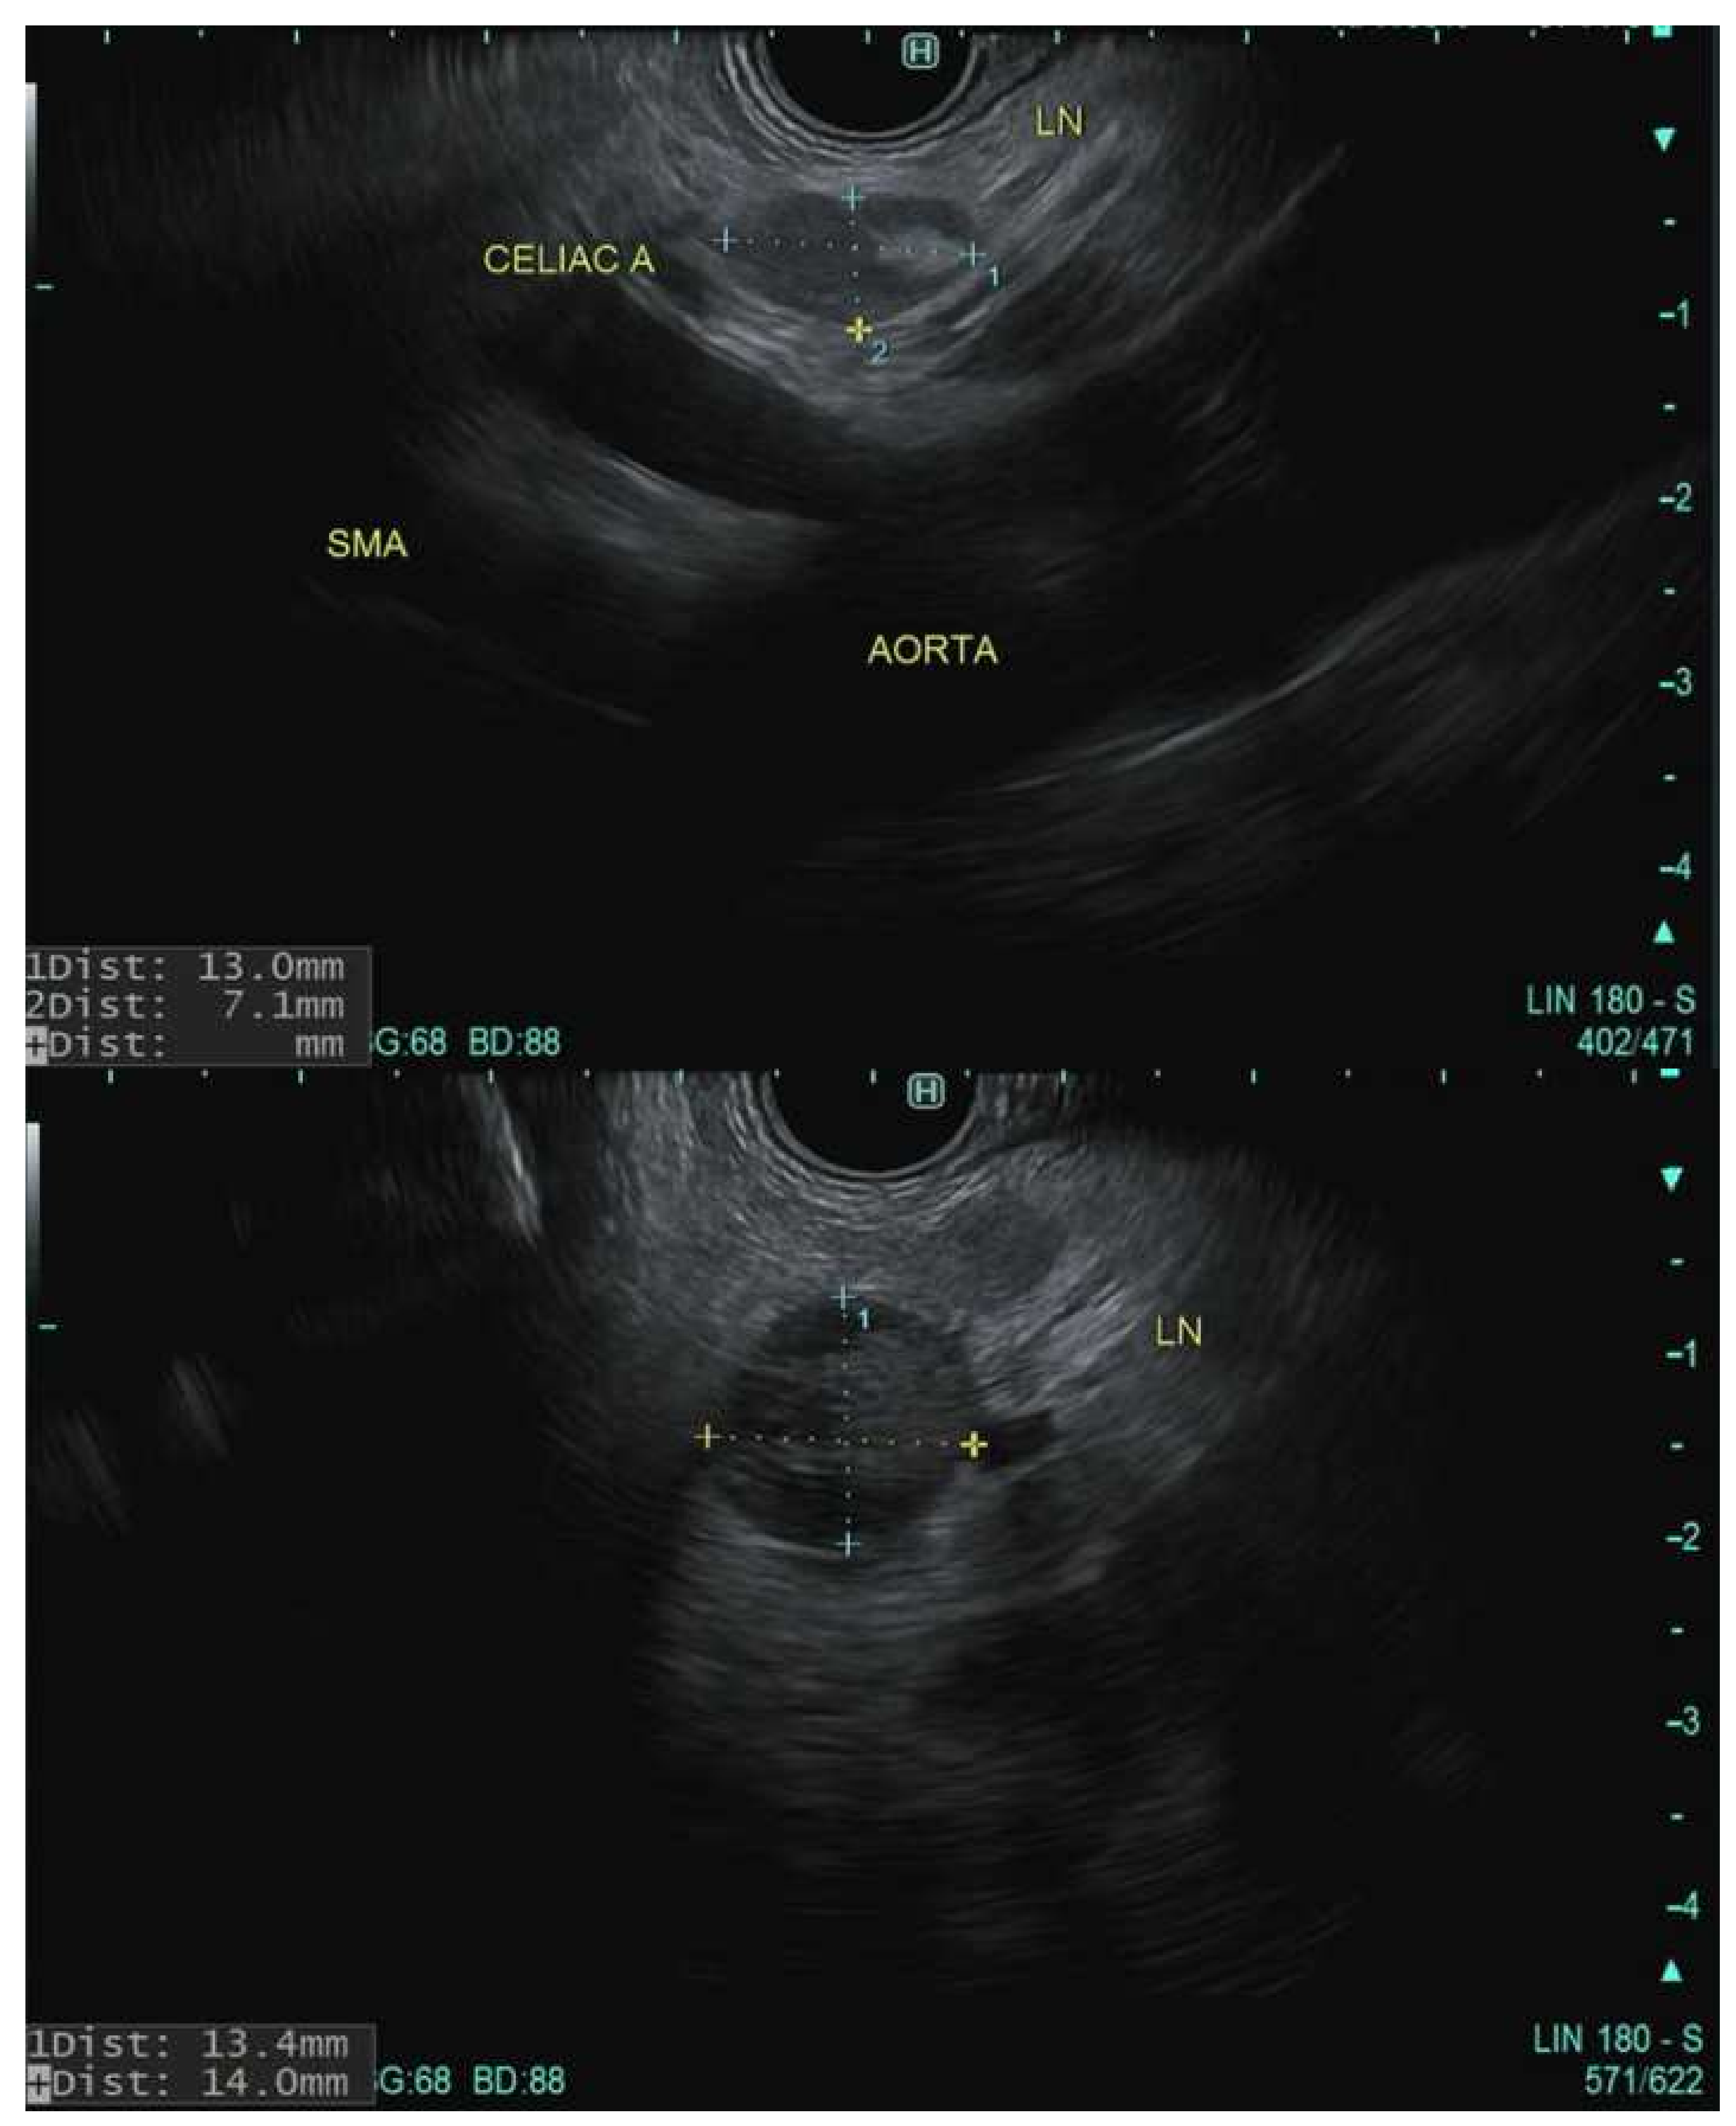

7. Staging

- Yang, R.; Lu, M.; Qian, X.; Chen, J.; Li, L.; Wang, J.; Zhang, Y. Diagnostic accuracy of EUS and CT of vascular invasion in pancreatic cancer: A systematic review. J. Cancer Res. Clin. Oncol. 2014, 140, 2077–2086. [Google Scholar] [CrossRef] [PubMed]

- Nawaz, H.; Fan, C.Y.; Kloke, J.; Khalid, A.; McGrath, K.; Landsittel, D.; Papachristou, G.I. Performance characteristics of endoscopic ultrasound in the staging of pancreatic cancer: A meta-analysis. JOP J. Pancreas 2013, 14, 484–497. [Google Scholar] [CrossRef]

- Rösch, T.; Dittler, H.-J.; Strobel, K.; Meining, A.; Schusdziarra, V.; Lorenz, R.; Allescher, H.-D.; Kassem, A.M.; Gerhardt, P.; Siewert, J.-R.; et al. Endoscopic ultrasound criteria for vascular invasion in the staging of cancer of the head of the pancreas: A blind reevaluation of videotapes. Gastrointest. Endosc. 2000, 52, 469–477. [Google Scholar] [CrossRef]

- Rosch, T.; Dittler, H.J.; Lorenz, R.; Braig, C.; Gain, T.; Feuerbach, S.; Höfler, H.; Siewert, J.R.; Classen, M. Endosonographisches Staging des Pankreaskarzinoms. DMW Dtsch. Med. Wochenschr. 1992, 117, 563–569. [Google Scholar] [CrossRef]